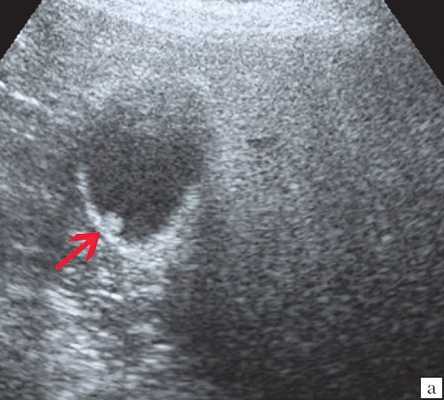

Ультразвуковое исследование органов брюшной полости (УЗИ) - наиболее доступный метод обследования желчных путей, по сути скриннинг-метод. Чувствительность его на предмет выявления расширения общего желчного протока составляет до 90%. Однако, не всегда специалисту ультразвуковой диагностики удается осмотреть терминальный отдел холедоха (зону слияния общего желчного и панкреатического протоков, и их впадения в двенадцатиперстную кишку), т. е. очень важный для постановки правильного диагноза отдел. Осмотру может мешать газ или жидкость (даже в небольшом количестве), находящиеся в кишке.

- УЗИ брюшной полости. Используется, как скрининг для проведения дифференциальной диагностики печеночной и механической желтухи. Критерии УЗИ, по которым можно уверенно диагностировать механическую причину желтухи: деформация желчного пузыря или его увеличение, расширение (более 8 мм) холедоха, других протоков - более 4 мм, обнаружение конкрементов в протоках или в желчном пузыре, а также обнаружение опухоли головки поджелудочной железы или другой локализации в области желчных путей. Если протоки не изменены, в то время как печень диффузно изменена, то это говорит в пользу печеночного варианта желтухи, а не обтурационного. Однако, согласно статистике, по данным УЗИ установить обтурационный характер желтухи можно лишь в 75% случаев.